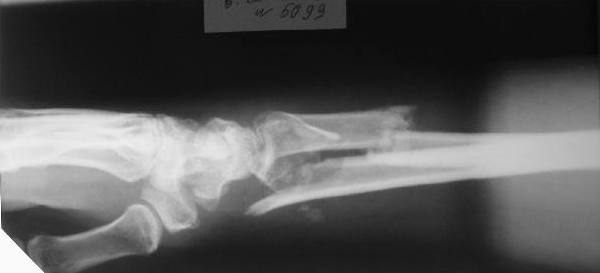

Больному 27 лет. Травма 2 месяца назад, проводилась закрытая репозиция. Контрольные снимки 3 недели назад (смотреть вложение).

Планируем провести открытую репозицию фиксацию пластинами.

Обдумываем, как провести репозицию? Предварительно провести дистракцию аппаратом внешней фиксации за нескольких дней до открытой репозиции или во время открытой репозиции?

Первоначальное впечатление: если край проксимального отломка лучевой кости не давит на срединный нерв и не нарушает скольжение сгибателей, то достаточно быстро пациент сможет вернуться к труду при продолжении консервативного лечения. Укорочение на 15 мм для неопорного (да и для опорного тоже) сегмента некритично. Имеющиеся осевые смещения вполне компенсируются запасом диапазона фукции суставов. Если край проксимального отломка мешает -- можно резецировать его, не разрушая сфорировавшегося к сегодняшнему дню сращения.